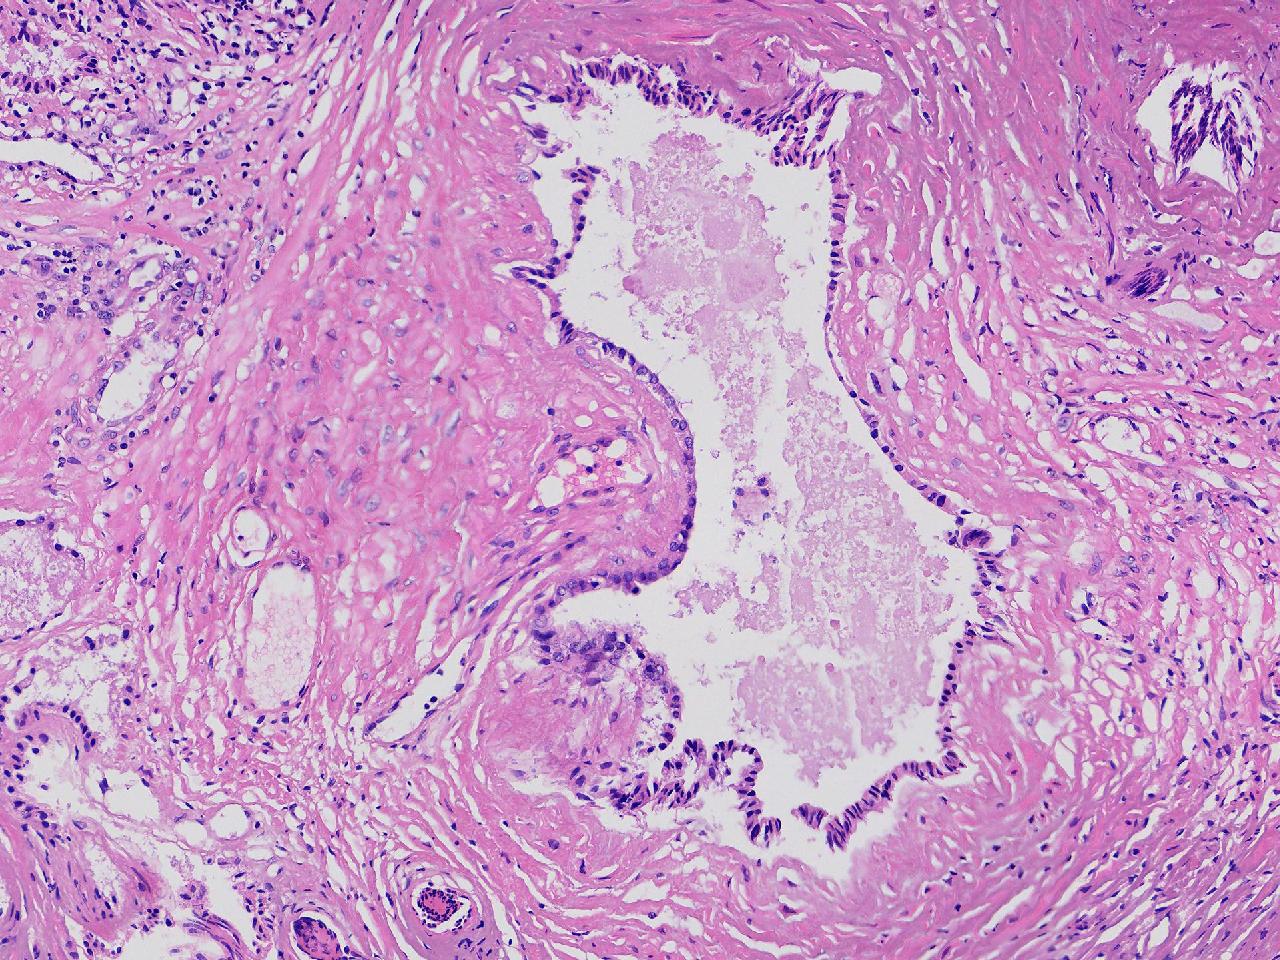

这些腺体有问题吗?

男,77岁,排尿困难2年,尿潴留3天。

标本名称

电切前列腺组织

图3